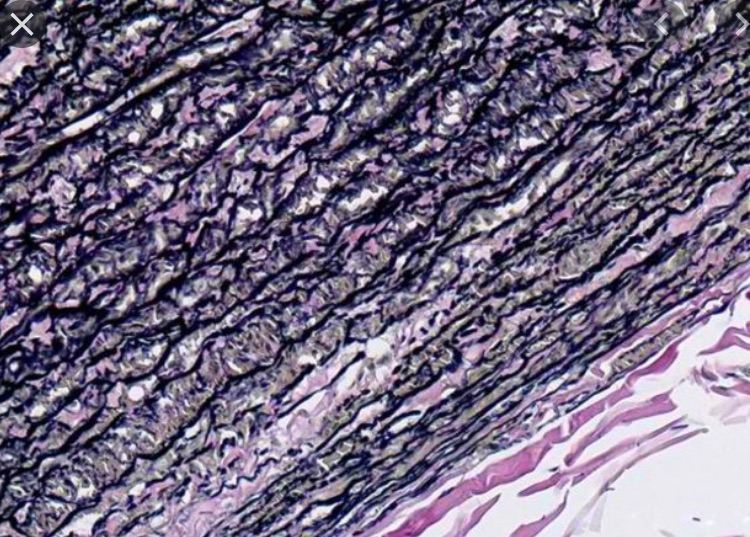

1 Tissue ประเภทใด

5 จากภาพเป็นเนื้อเยื่อชนิดใด

6 จงบอกชนิดของเนื้อเยื่อ

12 จากภาพคือ เนื้อเยื่อชนิดใด

13 จากภาพ คือเนื้อเยื่อใด

14 เนื้อเยื่อชนิดใด

15 จากภาพ คือเนื้อเยื่อใด

16 จากภาพคือ เนื้อเยื่อใด

17 จากภาพคือเนื้อเยื่อชนิดใด

18 จากภาพคือเนื้อเยื่อชนิดใด

21 จากภาพคือเนื้อเยื่อชนิดใด

22 จากภาพคือเนื้อเยื่อชนิดใด

23 จากภาพคือเนื้อเยื่อใด